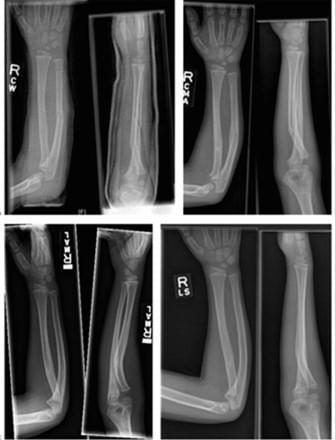

Distal radius and ulna fracture

- Distal radius 骨折原則上預後良好,如果<10歲可以接受dorsal tilting arond 10 degree. 大於10歲就不可以>10度。

- 另外如果有生長板受傷需要跟家長解釋會有生長板受損之風險。SH type 1 跟2約5%。SH 3-5約10-40%。

- ulna的生長板受傷有很高的機會會停止生長,須長期觀察。

Radial or ulna shaft fracture or deformity

- 除非年紀很小,發生在shaft及靠近手肘的骨折,不要太期望會remodeling.

- 如果interosseous space狹窄,至少要進行closed reduction and casting. 如果復位不好,就進開刀房reduction.

- Long arm cast需要cast index: 0.8。一定要跟家長告知compartment syndrome風險